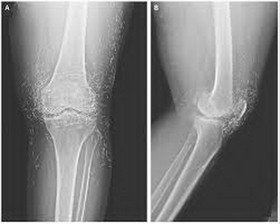

بررسی ایمپلنت انگل بلت برای درمان انحراف مفصل زانو در کشور

یک عضو مرکز تحقیقات استخوان، مفصل و بافتهای وابسته دانشگاه شهید بهشتی با بیان اینکه تحقیقی با عنوان مقایسه کاربرد پلاکهای LCP و انگل بلت در درمان انحراف مفصل زانو برای نخستین بار در کشور انجام شده است، تاکید کرد: این تحقیقات به دنبال مقایسه میزان عوارض و دوام انجام جراحی با هریک از پلاکهای LCP و انگل بلت در درمان انحراف زانو است که دارای مزایای درمانی ویژه با کاهش عوارض پس از عمل است و صرفه جویی ارزی قابل توجهی به همراه دارد.

فرشاد صفدری در گفت وگو با خبرنگار ایسنا منطقه علوم پزشکی تهران، با اشاره به اینکه اغلب مراجعه کنندگان برای درمان انحراف شدید زانو زنان هستند که در این افراد هنوز مفصل زانو به آرتروز تبدیل نشده است، گفت: برش قسمت پایینی استخوان ران و تغییر زاویه مفصل زانو روش درمانی مرسوم انحراف شدید زانو است که می بایست پس انجام عمل جراحی استخوان بریده و فیکس شود.